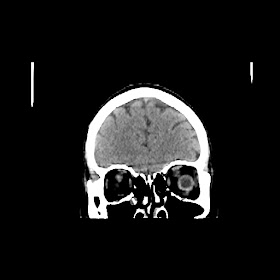

A 50 years old woman with headache, back pain, ghabrahat